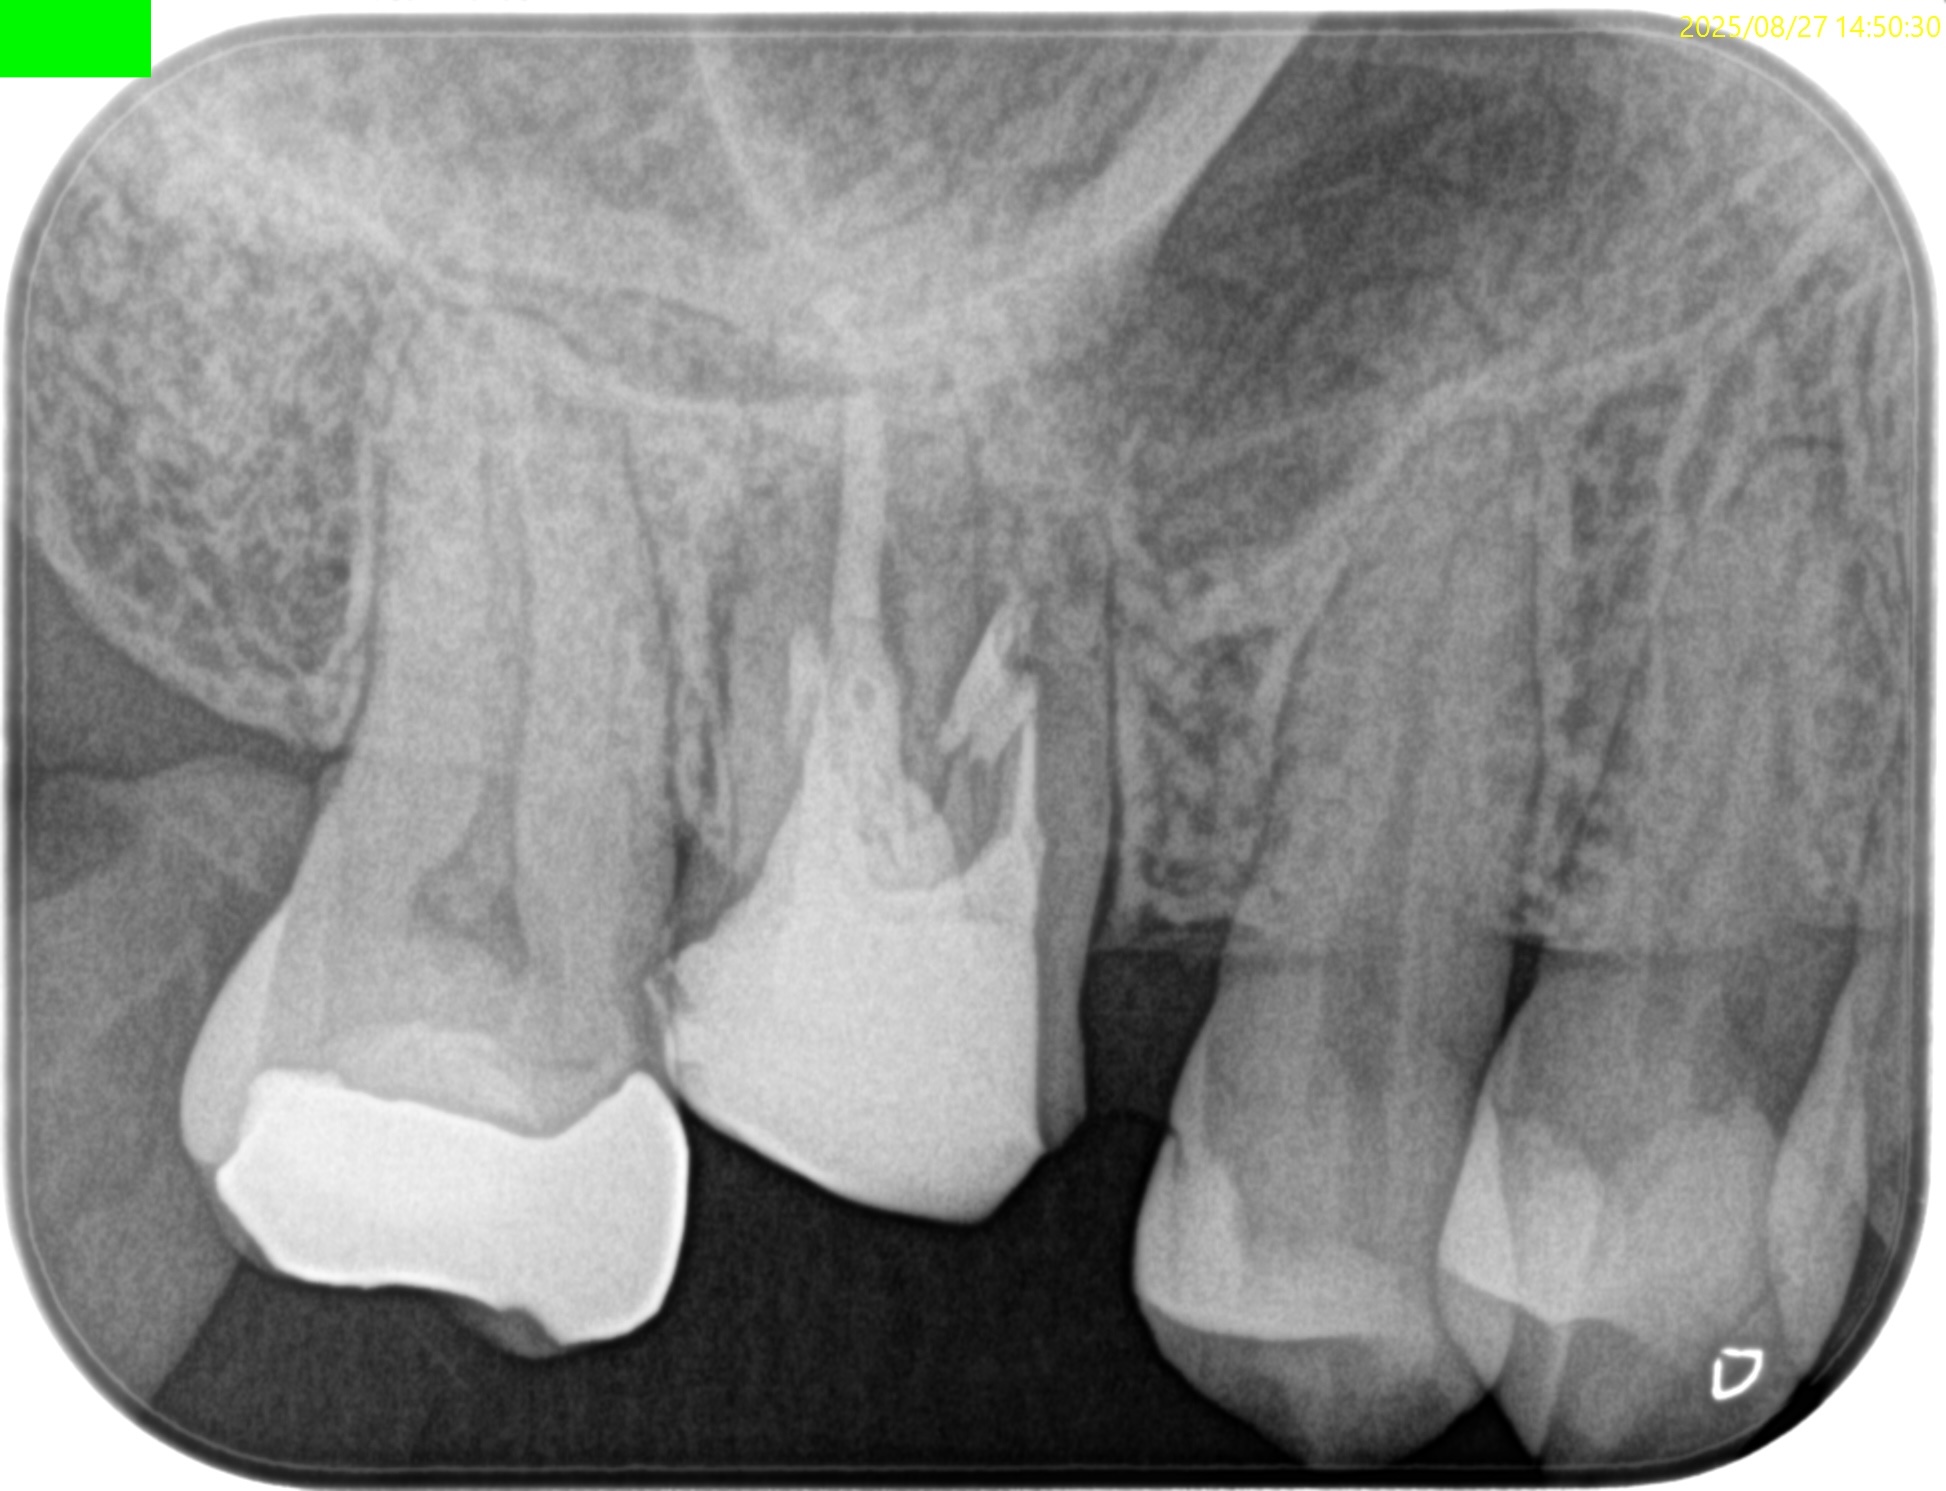

MB,DB,P全ての根管に根尖病変がある。

PのP側皮質骨はかなり減少している。

これが歯周病が原因か?と言えば、

術前の検査で歯周ポケットが正常値(Within Normal Limit)なため、恐らくエンドが原因でこのようになっているのだろう、と推測できる。

#3 MB, DB Apicoectomy 7M recall(2026.3.30)

7ヶ月前と比較した。

劇的に歯槽骨の開創は回復している。

そしてP根だが、根尖病変の治癒とともに口蓋側の骨欠損が大きく回復しているのがわかる。

これは単純にエンドだけの問題であったのだ。

エンドの治療のみでここまで回復していることがこの歯内療法の治療のパワーを示している。

HyFlex EDM #60.02でわずか数mm形成しただけなのに、ここまで歯槽骨が回復している。